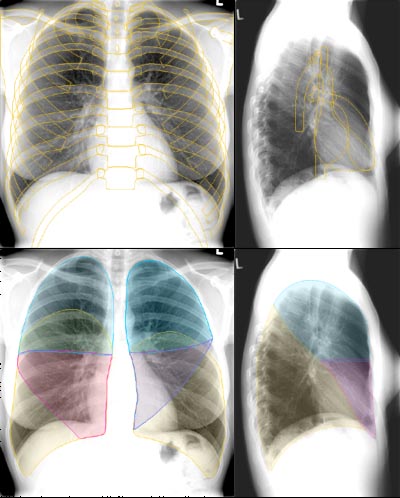

Röntgenzeichen

Voraussetzung zur Interpretation von Thoraxröntgenbildern ist die Kenntniss der in diesen Bildern erkennbaren Röntgenzeichen. Da sich dieses Lernmodul erst in Planung befindet, verweisen wir auf unten stehende Übersichtsartikel.